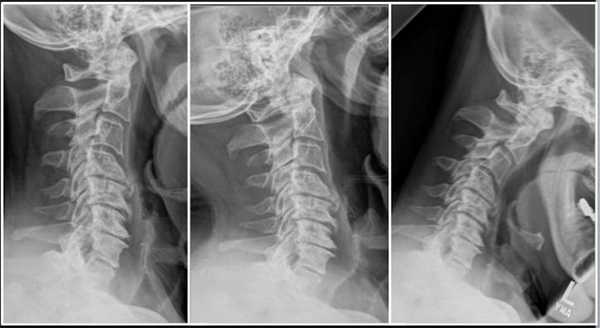

Импланты шейного отдела позвоночника на рентгене.

Если клиника симптомов не поддается консервативной терапии или неинвазивные способы не могут быть задействованными ввиду сильно прогрессирующего стеноза, назначается операция. Вмешательство предполагает использование декомпрессионной ламинэктомии под общим наркозом. При комбинированной проблеме, например, вместе с грыжей, ее сочетают с микродискэктомией и спондилодезом. При спондилодезе осуществляют скрепление смежных позвонков металлическими фиксаторами (стержнями, пластинами, крючками и пр.), установку межтеловых имплантатов или вживление костного трансплантата с металлической гильзой.

Установка металлической конструкции.